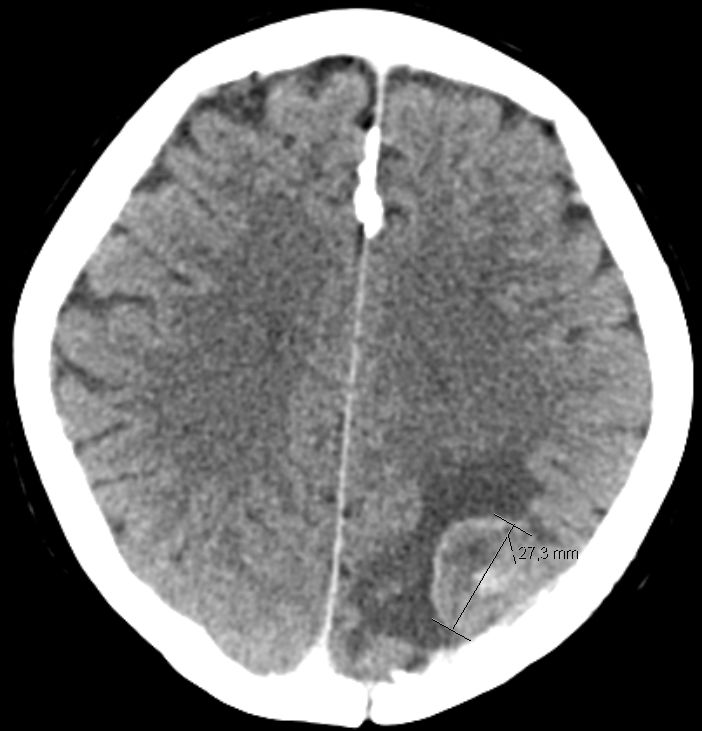

| Hirnmetastase | 48-jährige Frau, die vor 4 Jahren ein DLBCL Stadium IVa mit Bulk rechts inguinal, Lymphknoten mediastinal axillär links, Milzvergrößerung und pulmonale Infiltration hatte. 8mal R-CHOP, RT der rechts inguinalen Lymphknoten mit 26 Gy. Vor 5 Monaten Tumor linker Hilus und Hirnmetastase links occipito-parietal: Histologie: großzelliger neuroendokriner Tumor. Entfernung der Hirnmetastase, RT Neurocranium. 6 x Carboplatin/Etoposid: PR des Lungentumors, vitaler Resttumor des Gehirns | |||||||||||||||||||

CT: vitales Tumorgewebe 2 Monate nach RT.![]() | |||||||||||||||||||